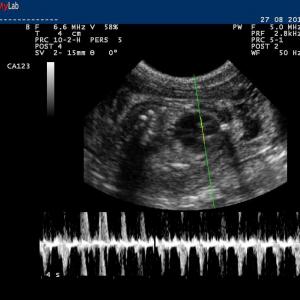

Auch in der Veterinärmedizin wird das schonende Verfahren der Ultraschalldiagnostik zunehmend eingesetzt. Wir verwenden es im Bereich der Abdominal- und Trächtigkeitsdiagnostik .